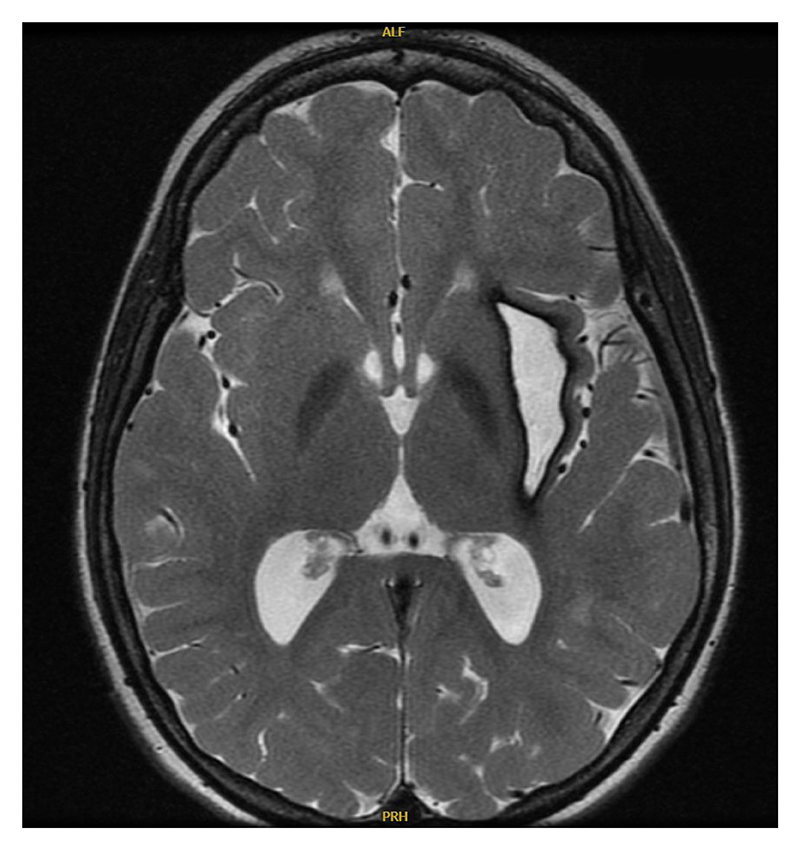

His family history is unremarkable for any autoimmune or autoinflammatory diseases, including interferonopathies. He has older siblings who are healthy. There is no history of parental consanguinity. Additional laboratory workup revealed hypergammaglobulinemia (IgG, 1,960 mg/dL), positive antinuclear antibodies (1:160), and hypothyroidism. Brain MRI and magnetic resonance angiography (MRA) showed new T2 hyperintensities, a chronic hemorrhagic cavity in the left subinsular region (Figure 1), and a right medial cerebral artery (MCA) aneurysm. Serial imaging noted aneurysm progression, and angiography at age 14 years revealed persistence of the right MCA aneurysm and a new aneurysm on the left lenticulostriate artery (Figure 2). Endovascular embolization was unsuccessful, and open craniotomy was deferred due to surgical risk. Repeat MRA at age 16 years showed stable aneurysms.

Figure 1: Brain MRI shows T2 hyperintensities and a chronic hemorrhagic cavity in the left subinsular region.